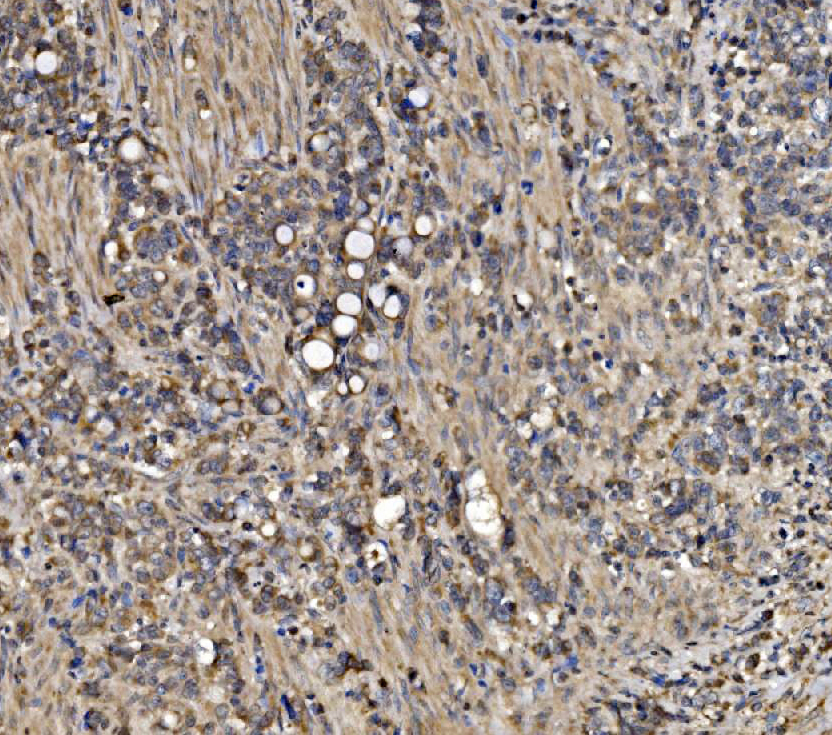

IHC analysis of ATG9A using anti-ATG9A antibody (A03757-3).

ATG9A was detected in a paraffin-embedded section of human grastric cancer tissue. Biotinylated goat anti-rabbit IgG was used as secondary antibody. The tissue section was incubated with rabbit anti-ATG9A Antibody (A03757-3) at a dilution of 1:200 and developed using Strepavidin-Biotin-Complex (SABC) (Catalog # SA1022) with DAB (Catalog # AR1027) as the chromogen.